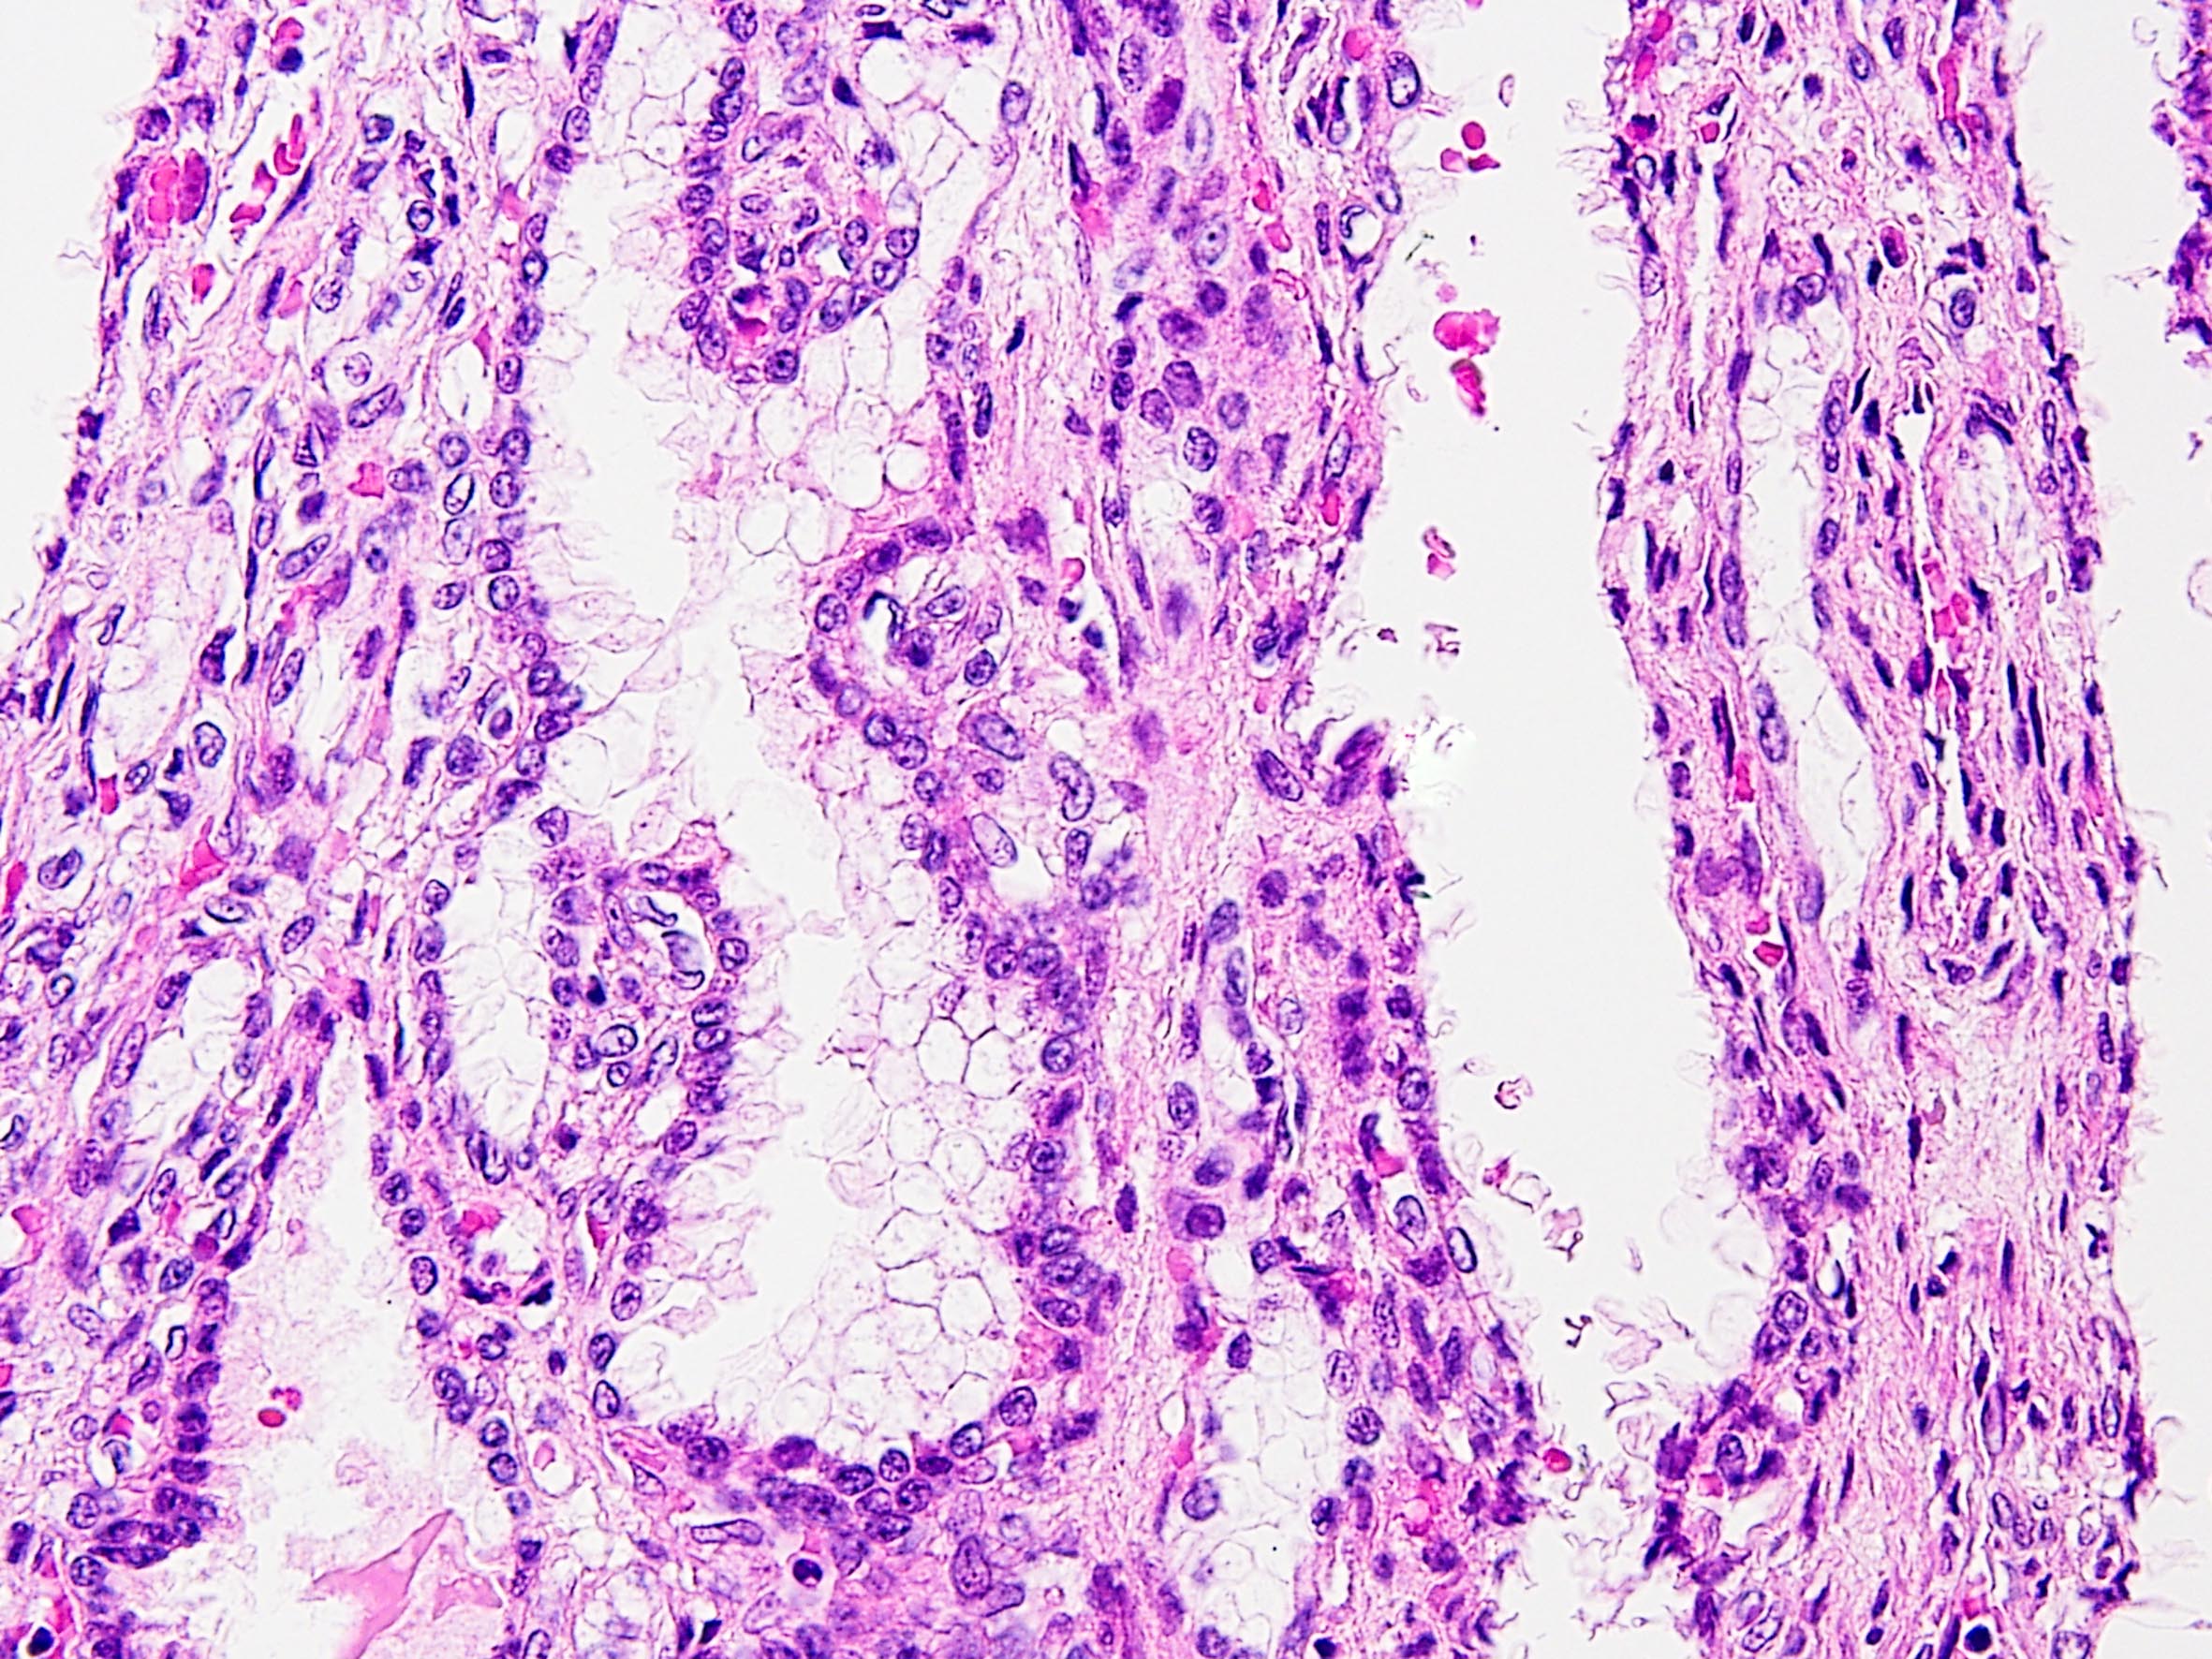

Consensus grade: Multilocular cystic renal neoplasm of low malignant potential

just see focally features of clear cell papillary RCC (last slide) but the overall appearance is multilocular cystic renal neoplasm...... |

Multilocular cystic renal neoplasm of low malignant potential